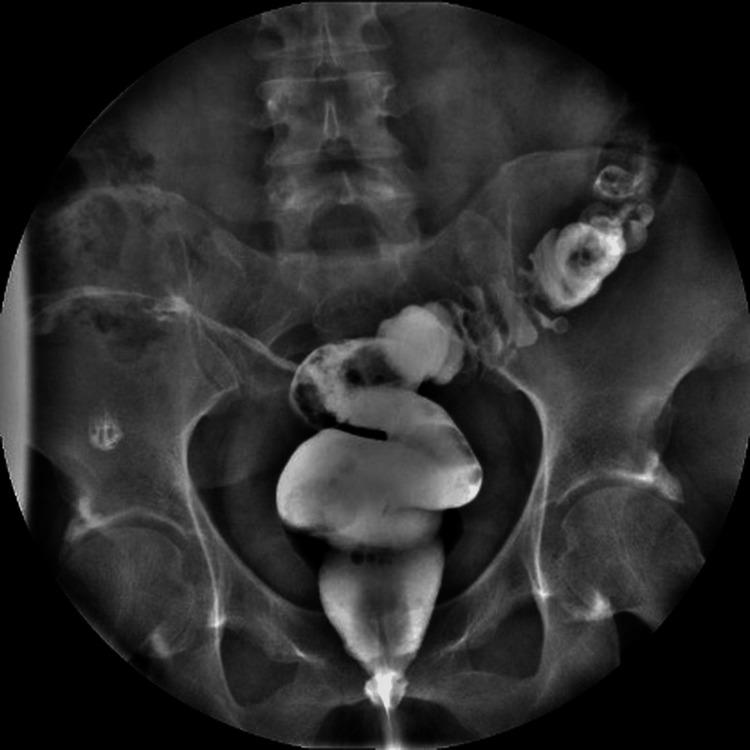

Colocutaneous fistulas are a rare but challenging complication of abdominal and pelvic surgery. Their surgical management can be difficult, especially when associated with multiple failed treatments. Transanal minimally invasive surgery (TAMIS), initially designed for local excision of rectal tumors, has been increasingly used in complex benign conditions. We present the case of a 41-year-old female patient with a chronic rectocutaneous fistula that developed following a hysterectomy and had persisted despite four failed endoscopic clip placements. The patient also reported intermittent passage of air through the vagina; however, no rectovaginal communication was identified through imaging, endoscopy, or intraoperative exploration. The fistula orifice was located 15-16 cm from the anal verge and was approached using a TAMIS platform, allowing for direct endoluminal access and precise intracorporeal suturing. The procedure lasted 65 minutes, with minimal blood loss. The patient had an uneventful recovery and was discharged 48 hours later. Long-term follow-up at three years demonstrated complete and durable resolution of the fistula, without recurrence or complications. This case illustrates the utility of TAMIS in the definitive management of complex post-hysterectomy rectal fistulas and supports its use as a safe and effective alternative to more invasive procedures in selected non-oncologic cases.

结肠皮肤瘘是腹部和盆腔手术中一种罕见但具有挑战性的并发症。其手术治疗可能很困难,尤其是在与多次治疗失败相关时。经肛门微创手术(TAMIS)最初设计用于直肠肿瘤的局部切除,越来越多地用于复杂的良性疾病。我们报告了一例41岁女性患者,她在子宫切除术后出现慢性直肠皮肤瘘,尽管进行了四次内镜夹闭术均失败,但瘘仍持续存在。患者还报告有气体间歇性经阴道排出;然而,通过影像学、内镜检查或术中探查均未发现直肠阴道瘘。瘘口距肛缘15 - 16厘米,使用TAMIS平台进行处理,可实现直接腔内入路和精确的体内缝合。手术持续65分钟,失血极少。患者恢复顺利,48小时后出院。三年的长期随访显示瘘完全持久愈合,无复发或并发症。该病例说明了TAMIS在子宫切除术后复杂直肠瘘的确定性治疗中的实用性,并支持其作为选定非肿瘤病例中更具侵入性手术的安全有效替代方法。